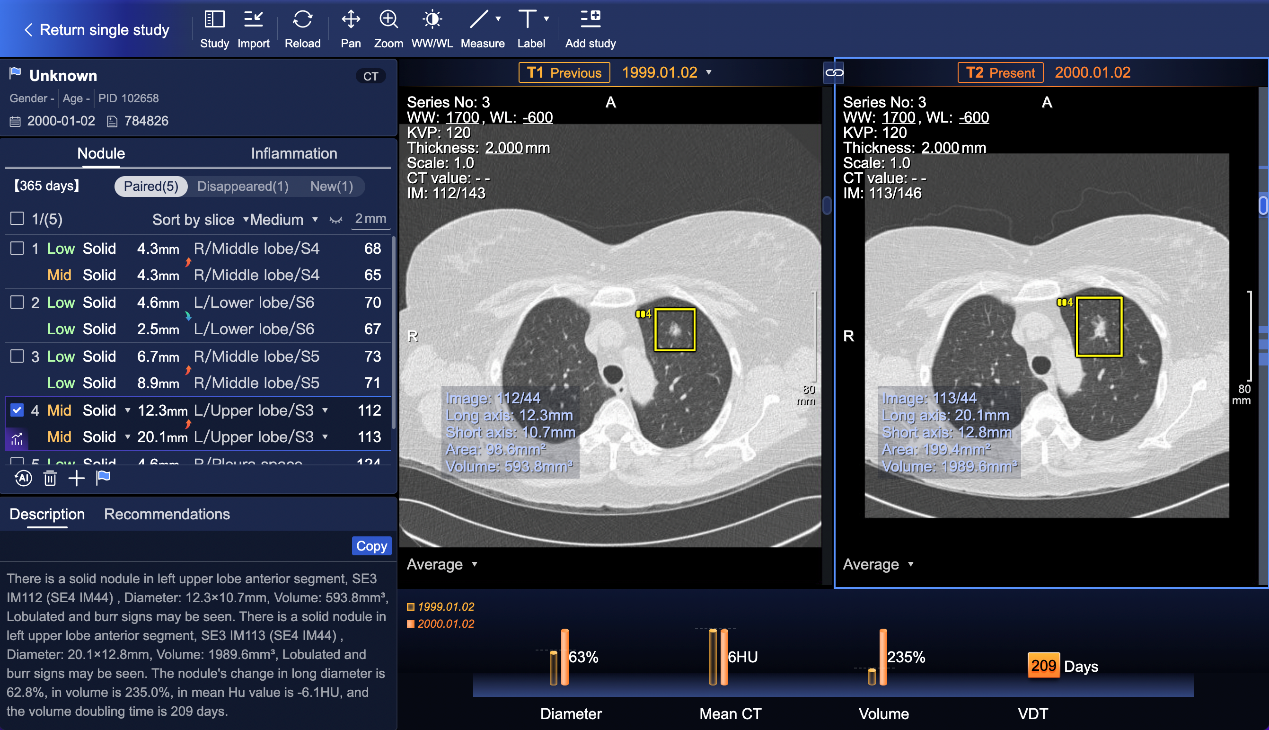

SenseCare®胸部CT智能分析系统-随访管理模块(商汤科技供图)

IHH医疗对新技术临床集成与实际应用价值有严格的评估标准。通过紧密的本地化集成和严谨的临床验证,2024年,SenseCare®系统正式在IHH医疗体系中部署运行。SenseCare®系统凭借领先的算法与三维后处理技术,在病灶识别与随访管理方面展现出较强的应用价值。通过自动检测并定位毫米级肺结节、清晰标注其形态与特征、自动提示风险等级,实现高效筛查,提升检出率与准确性,降低了微小病灶的漏诊风险。

更重要的是,它能智能追踪同一结节在不同时期影像中的动态变化,通过自动计算结节的直径、密度及生长速度等关键指标,为医生制定后续复查或干预方案提供客观的决策依据,有力支持了肺结节筛查与随访工作向智能化、标准化、个性化发展。